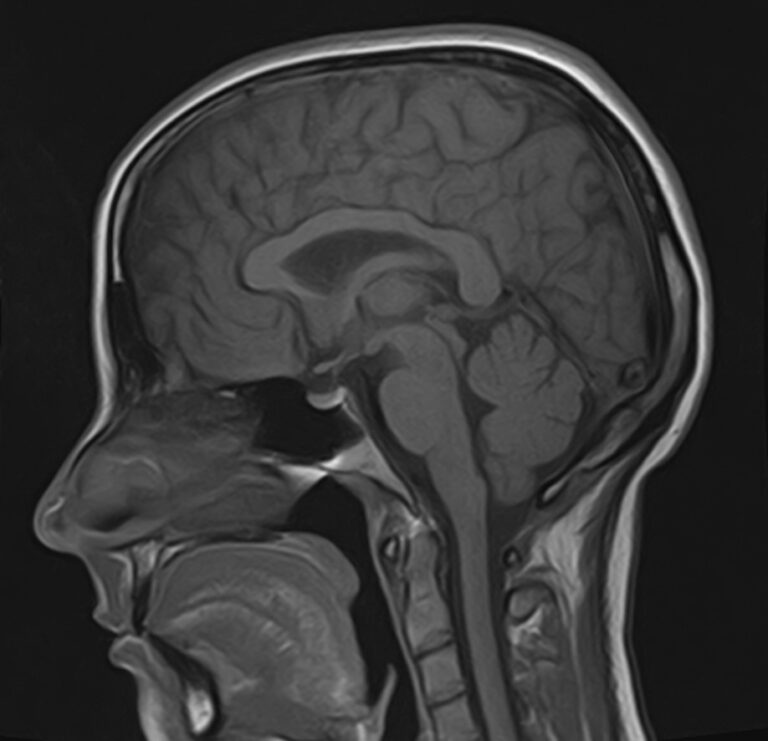

В клинике «Доступная медицина» можно пройти комплексное обследование, включающее в себя несколько протоколов сканирования близко расположенных друг от друга анатомических областей – шейного отдела позвоночника и головного мозга. Метод комплексного обследования оценивает состояние всех структур головного мозга и шейного отдела позвоночника. При этом дополнительные протоколы обследования позволяют визуализировать крупные сосуды шеи и сосудистую сеть головного мозга.

Сканирование проводится на современном высокопольном магнитно-резонансном томографе закрытого типа TOSHIBA VANTAGE TITAN 1,5 Тесла. Магнитно-резонансный томограф производит послойное сканирование исследуемой зоны в разных плоскостях, затем при помощи компьютерных программ преобразует полученные данные в трехмерные изображения. При этом кровеносная система реконструируется как вместе с окружающими тканями, так и отдельно без них.

• очаги ишемического и геморрагического инсульта, область поражения, признаки отека головного мозга, стадию развития заболевания;

• характерные признаки дегенеративных заболеваний головного мозга (болезнь Альцгеймера, старческая деменция, болезнь Паркинсона), определить изменения коры головного мозга и подкорковых структур;

• поражение структур головного мозга на фоне травм, гематомы головного мозга;